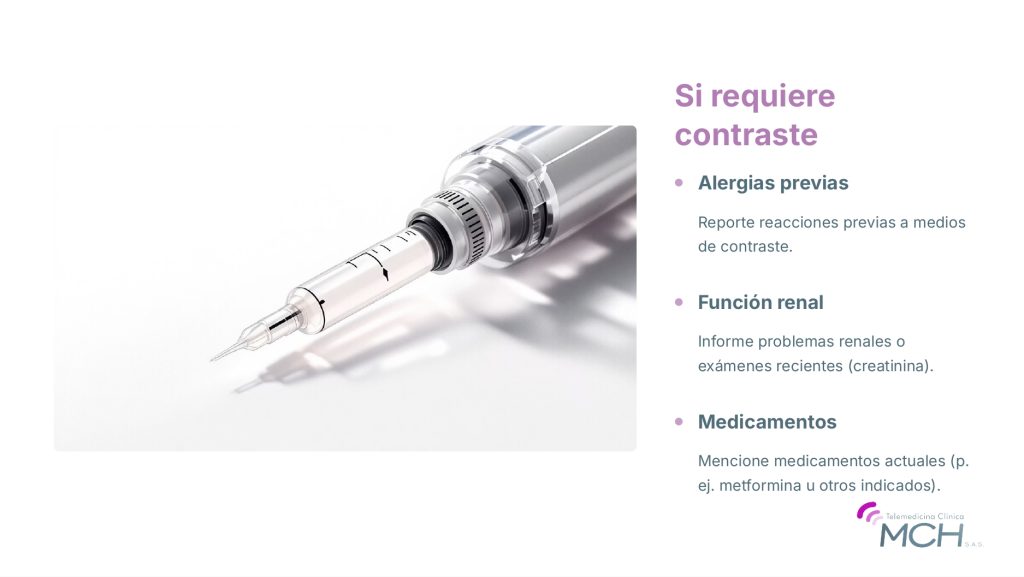

Este estudio (en inglés, National Lung Screening Trial [NLST]) consistió en un estudio clínico abarcador que investigó el uso de la LDCT del tórax para detectar el cáncer de pulmón. La tomografía computarizada del tórax provee imágenes más detalladas que una radiografía del tórax y es más eficaz al detectar pequeñas áreas anormales en los pulmones. La TC de baja dosis del tórax usa menores cantidades de radiación que la TC del tórax convencional y no requiere el uso de una sustancia de contraste a través de una línea intravenosa (IV).

La LDCT también expone a las personas a una pequeña cantidad de radiación con cada estudio. Esta radiación es menor a la que se recibe cuando se hace la tomografía convencional, pero la dosis es mayor que la emitida cuando se realiza una radiografía de tórax. Algunas de las personas que se someten a pruebas de detección pueden necesitar más tomografías computarizadas, lo que significaría más exposición a la radiación. Como consecuencia de la exposición a esta radiación, algunas pocas personas de cada decena de miles pueden padecer posteriormente cáncer de seno (mama), pulmón o tiroides.